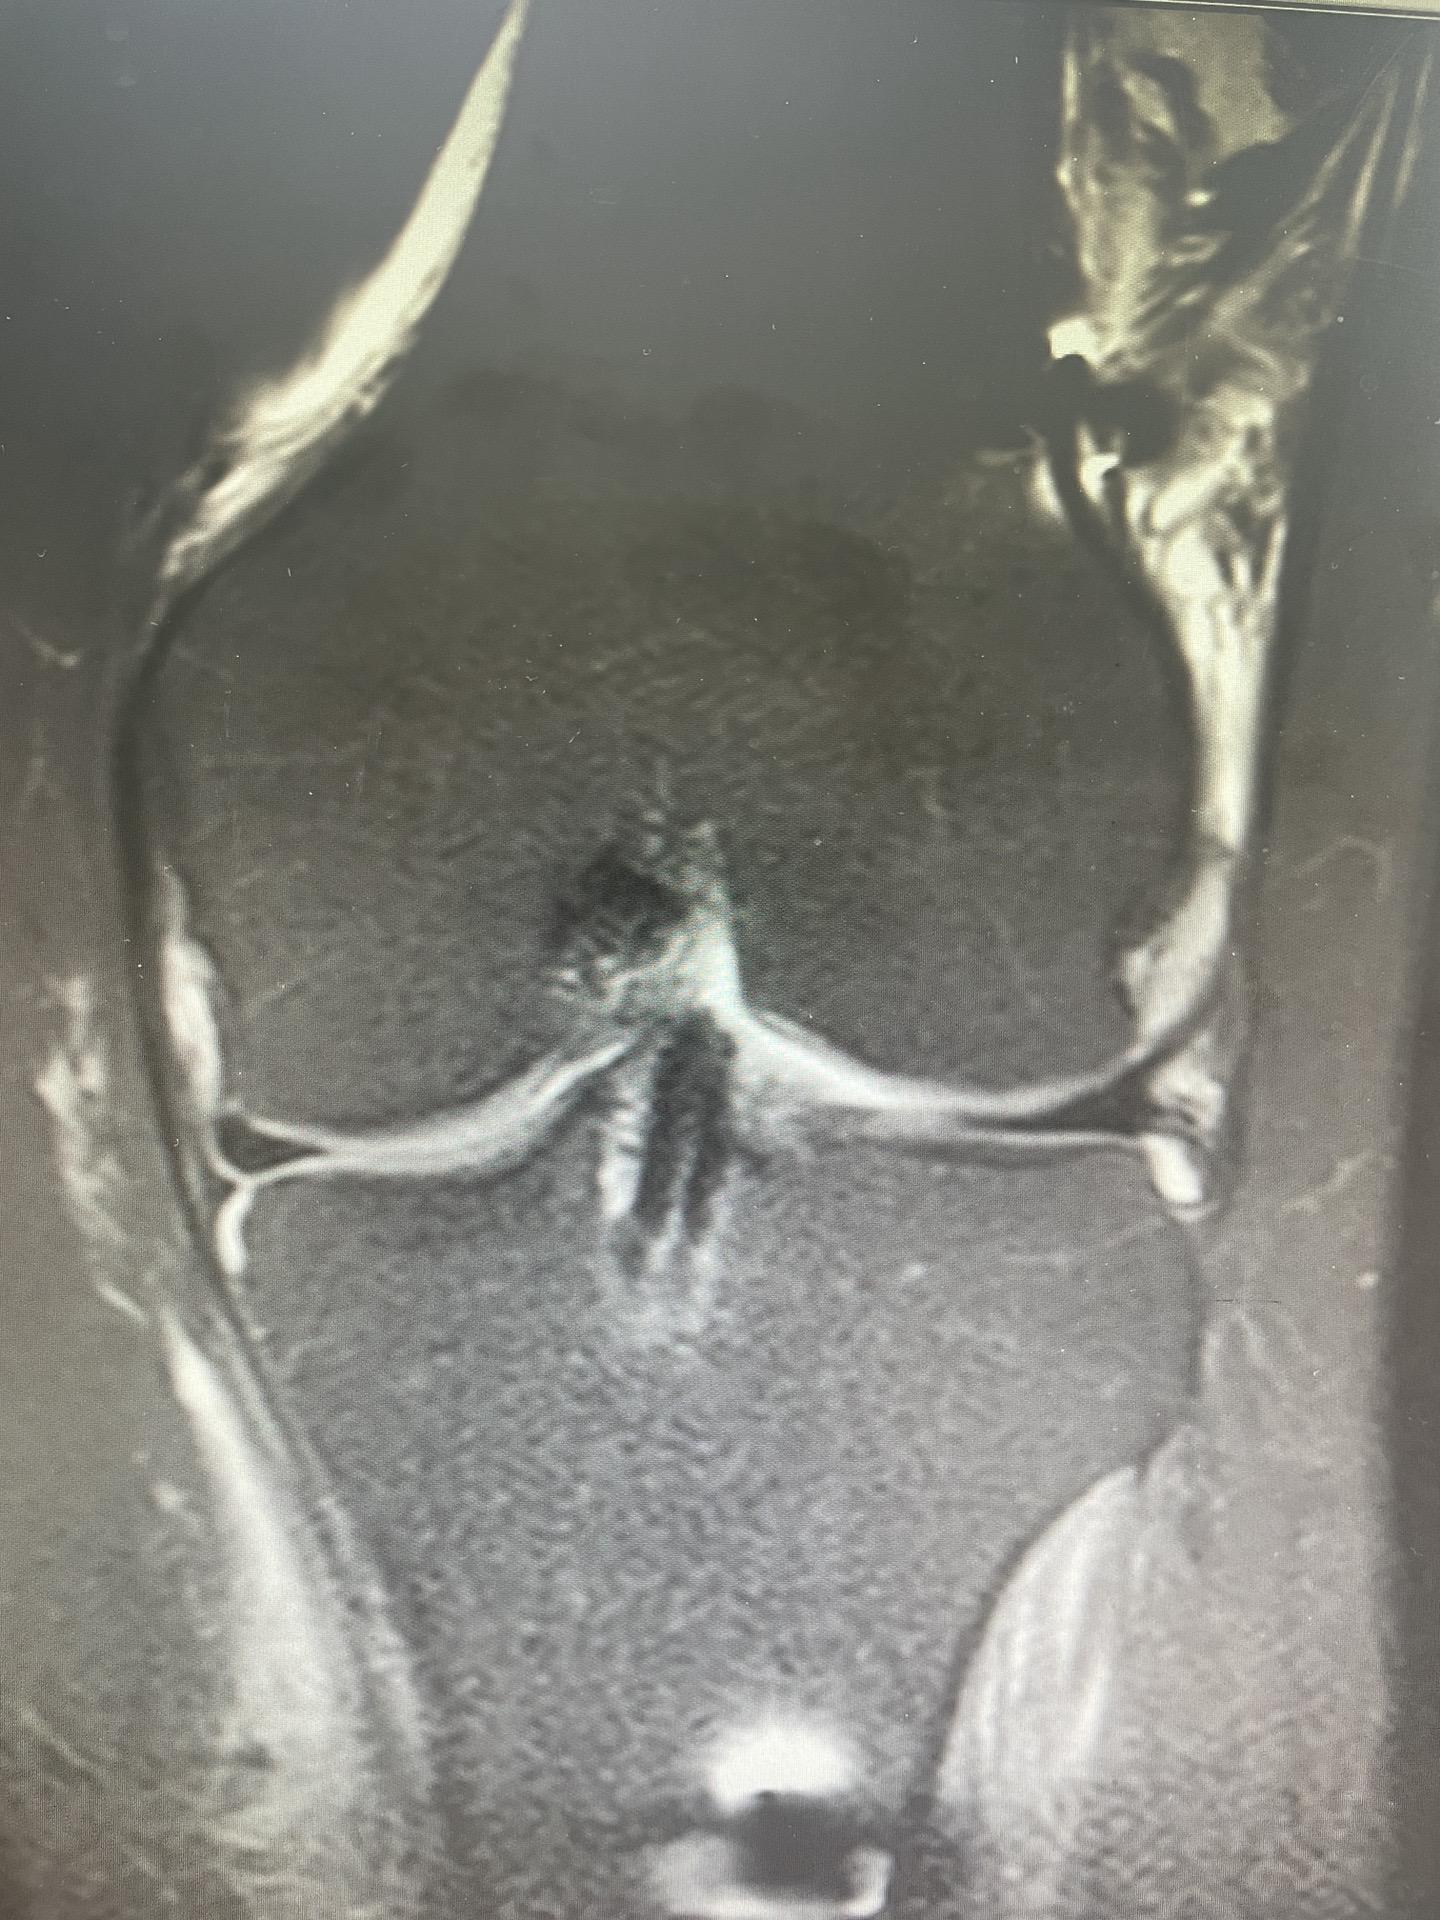

前交叉韧带重建。面对前交叉韧带的断裂,我们选择重建。希望这根强大的移植体,能为他撑起一片天,让他再次在运动场上放飞自我。前交叉韧带重建 前交叉